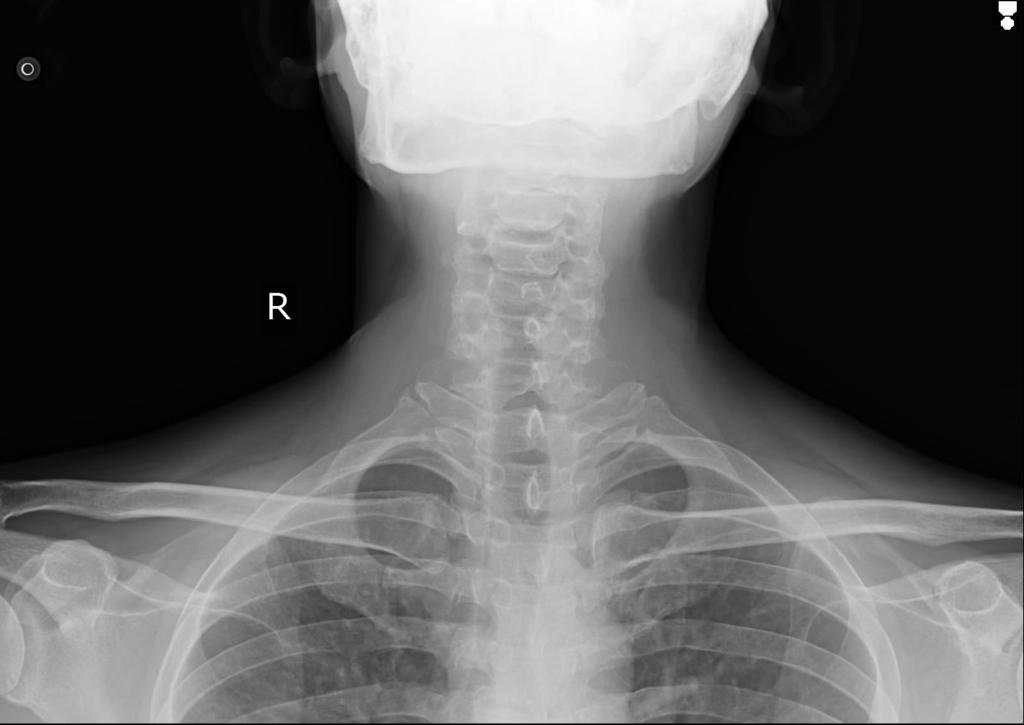

RS- Position of trachea central, vesiclular breath sounds +

L ISA Inspiratory wheeze +

L inspiratory crepitations ISA, IAA